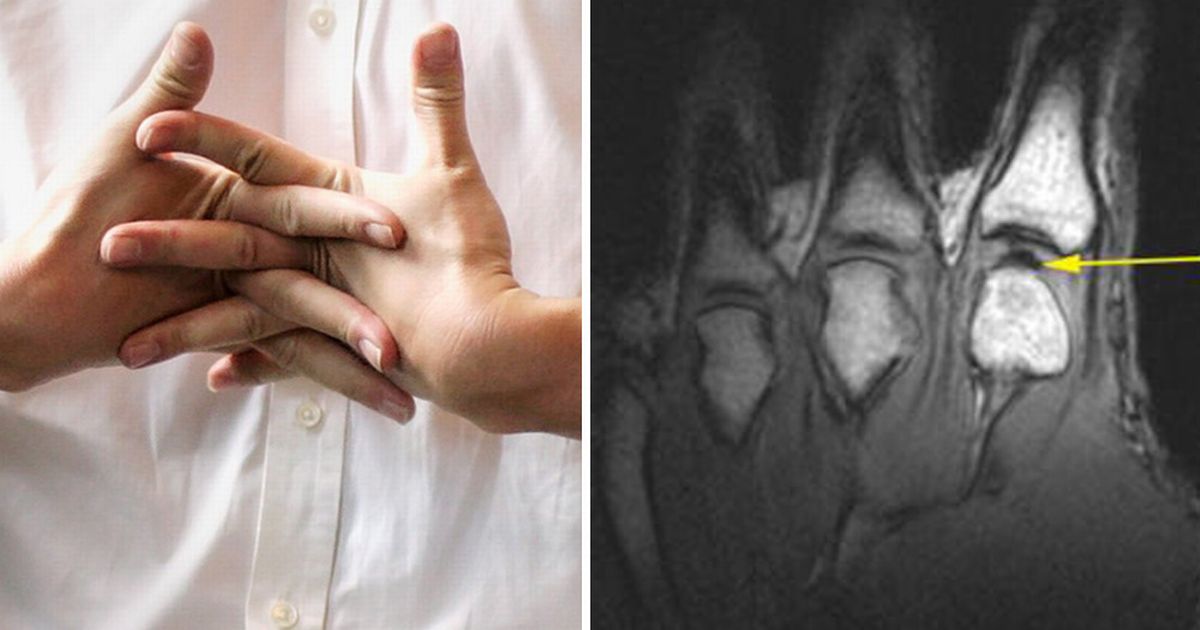

Ο ενοχλητικός θόρυβος που κάνει ο αγκώνας σας όταν τεντώνετε το χέρι σας ή το τρίξιμο που ακούτε στο ισχίο σας, σίγουρα δεν σας ενοχλεί και δεν σας κάνει να ασχολείστε με την ουσία του πράγματος. Πολλοί θεωρούν ότι ο ήχος αυτός των αρθρώσεων οφείλεται στην ηλικία και άλλοι σε αρθρίτιδα. Ο ήχος αυτός παράγεται μετά από κίνηση των δακτύλων,  των ισχίων, των γονάτων, των σπονδύλων στον αυχένα ή την οσφυϊκή μοίρα της σπονδυλικής στήλης, των ώμων, των κροταφογναθικών και άλλων αρθρώσεων. Ο ήχος αυτός ονομάζεται κριγμός  (ζωηρός ξηρός και επαναλαμβανόμενος ήχος). Στην αγγλοσαξονική ορολογία ονομάζεται “Cracking  the knuckles”.

Σημαντικό είναι να τονισθεί ότι παρά τον ήχο, η άρθρωση είναι ανώδυνη κατά την κίνηση και διαφέρει από την επώδυνη άρθρωση της χρόνιας οστεοαρθρίτιδας, που παράγει κατά την ψηλάφηση της έναν διαφορετικό ήχο.

Πολλοί ασθενείς με οστεοαρθρίτιδα ακούν ή αισθάνονται έναν χαρακτηριστικό ήχο (κριγμός) στις πληγείσες αρθρώσεις. Αυτό είναι πιο συνηθισμένο στα γόνατα.

Να σημειώσουμε πως, όταν εκδηλώνεται οστεοαρθρίτιδα στο γόνατο, ο χόνδρος που καλύπτει τα τελειώματα των οστών στην άρθρωση του γόνατος, καταστρέφεται. Μάλιστα μπορεί να καταστραφεί τόσο πολύ που το οστό να αρχίσει να τρίβεται απευθείας στο άλλο οστό, προκαλώντας έντονο πόσο στον ασθενή.